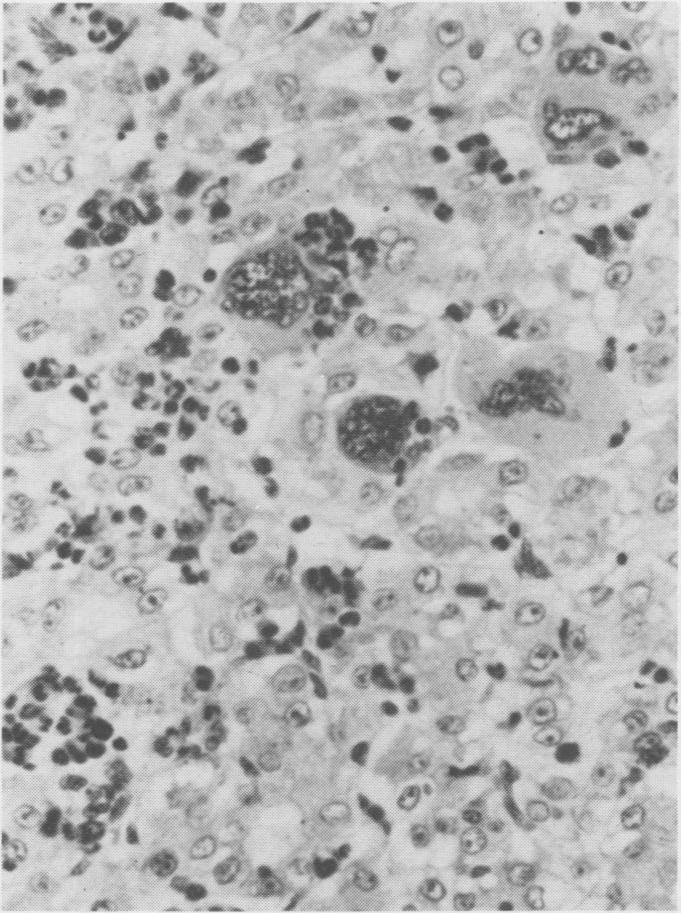

Eight bovine, two ovine and one porcine primary hepatocellular neoplasms were found during a five year survey of tumors from meat packing plants. The tumors varied in size and usually were yellow-grey. Some were encapsulated and divided into lobules by fibrous septa. The tumor cells closely resembled normal hepatocytes and were arranged in a trabecular pattern or in sheets with caverns or were a mixture of the two. Eosinophilic intranuclear inclusions were present in one bovine and one ovine case.